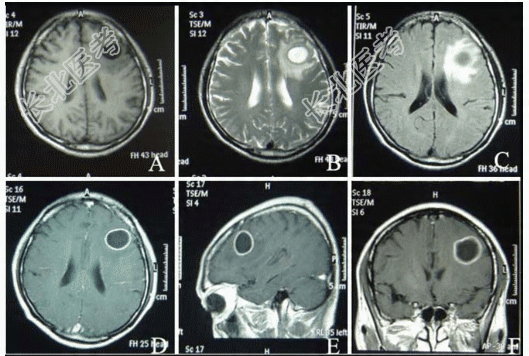

- 多项选择题4.提示:患者颅脑MRI平扫及增强扫描如图所示。该患者颅脑MRI平扫及增强扫描异常表现包括哪些

A、左额叶类圆形病变

B、左额顶叶类圆形病变

C、病变有一完整包膜,明显强化

D、病变有一完整包膜,但无明显强化

E、病变中心为短T1、短T2信号

F、病变中心为长T1、长T2信号

G、病变中心为长T1、短T2信号

H、病变中心为液性成分

I、病变周围明显水肿